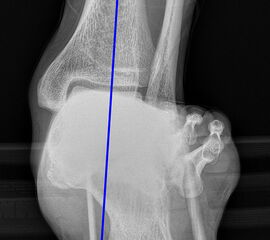

Achsen auf der lateralen Aufnahme

Die Grundlinie (blau) ist definiert durch den tiefsten Punkt der Sesambeine und den tiefsten Punkt des Kalkaneus.

CPA (Calcaneal pitch angle): Der Kalkaneus Inklinationswinkel liegt zwischen der Grundlinie (blau) und der plantaren Begrenzung des Kalkaneus (grün) (Norm 20,8 ± 4,1° 11, 15-39° (Zwipp 2014)).

LTCA (Lateral talocalcaneal angle): Der laterale talokalkaneare Winkel liegt wird gebildet aus der Talusachse (türkis) und einer Verbindungslinie zwischen dem Oberrand des Proc. ant. Calcanei und der dorsalen Begrenzung des Kalkaneus (gelb). (Norm: 33° Range 25-45°) 1213).

LTMA (Lateral talometatarsal angle, Syn. Meary’s angle): Der laterale talometatarsale Winkel wird gebildet aus der Achse des Os metatarsale I (rot) und der Achse des Talus (türkis). (Norm: 7,1 ± 10,8 11).